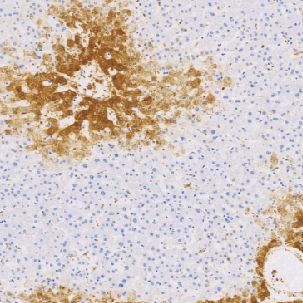

Glutamine Synthetase(GS)鼠抗人谷氨酷氨合成酶单克隆抗体

谷氯酷胺合成酶催化哺乳动物肝脏中谷氨酸和氨形成谷氯酷胺。在正常肝脏中,谷氨酷胺合成酶表达在中心周围的干细胞,而不表达于门静脉周的肝细胞。谷氨酷胺合成酶已被认为是肝细胞肝癌的标志物。谷氨酷胺合成酶在大多数肝细胞肝癌中表达,包括70%早期肝细胞肝癌和59%低分化肝细胞肝癌。

- 阳性部位:胞质

- 适用组织:石蜡切片

- 预处理:热修复